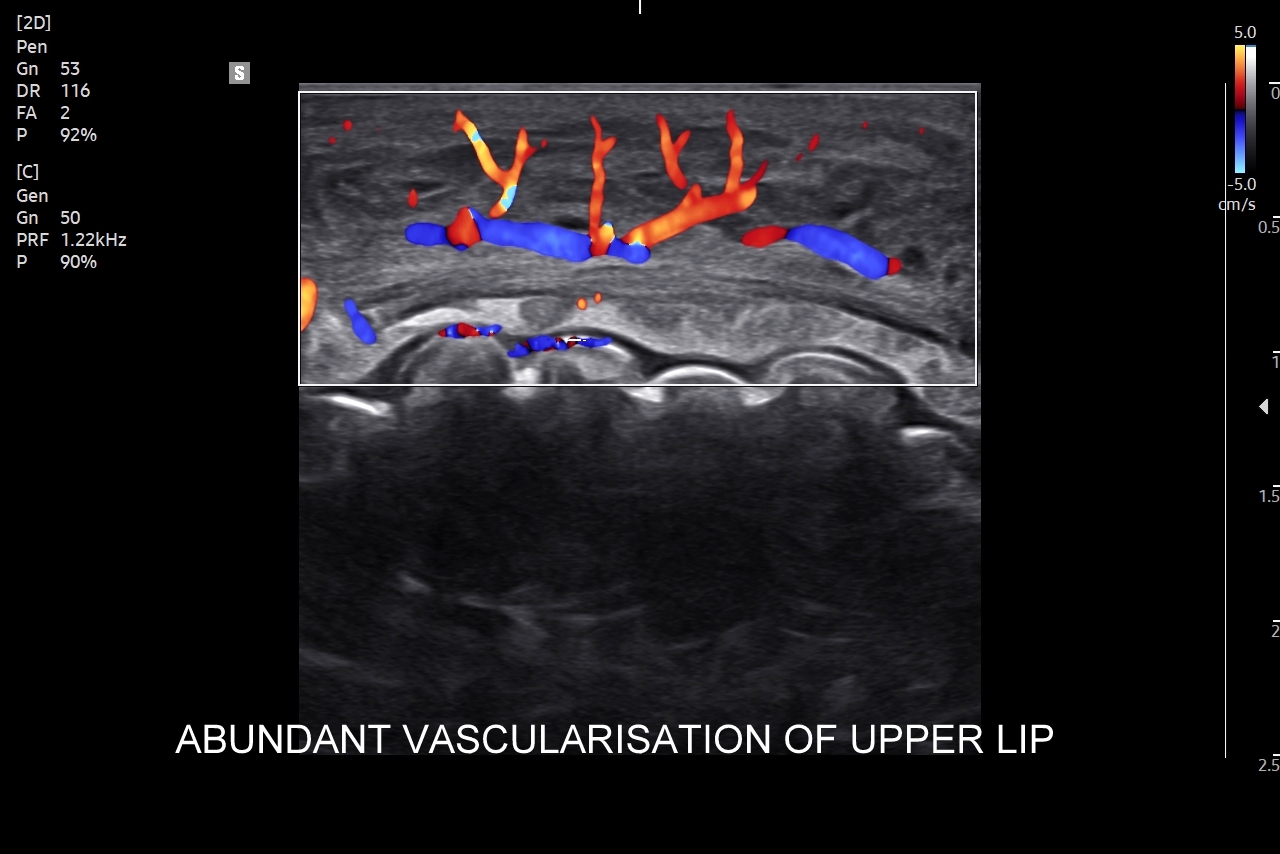

Badanie USG twarzy, często nie do końca fortunnie zwane USG skóry twarzy, to stosunkowo nowa metoda diagnostyczna wprowadzona we Wrocławiu do użytku przez dr Tomasza Szczepańskiego, a wykonywana w przypadku schorzeń z zakresu medycyny estetycznej, dermatologii, laryngologii, stomatologii i chirurgii. Wśród rozpoznań w badaniu USG skóry twarzy dominują choroby infekcyjne takie jak rozprzestrzeniające się w tkankach miękkich zapalenia i ropowice pochodzące od zapaleń zębów czy migdałków, powikłania ropne w przebiegu trądziku pospolitego lub różowatego, po iniekcjach wypełniaczy i po innych zabiegach z zakresu medycyny estetycznej. Kolejną dużą grupą patologii skóry twarzy są torbiele inkluzyjne, których przykładem są kaszaki, oraz guzy twarzy, wśród których dominują ziarniniaki jako odległe acz częste powikłanie depozycji wypełniaczy z kwasu hialuronowego.

USG twarzy wykorzystywane jest także do diagnozowania urazów twarzoczaszki, zarówno w obrębie tkanek miękkich (np. uraz zmiażdżeniowy tkanki podskórnej), jak i kości (np. złamanie kości jarzmowej, kości nosa); do oceny zaawansowania bruksizmu; oceny i kategoryzowania naczyniaków twarzoczaszki; diagnozowania zapaleń tętnic skroniowych; czy powikłań naczyniowych w medycynie estetycznej. Badanie USG twarzy służy również do oceny defektów kosmetycznych zarówno przed ewentualnymi zabiegami estetycznymi i plastycznymi, jak i po nich.